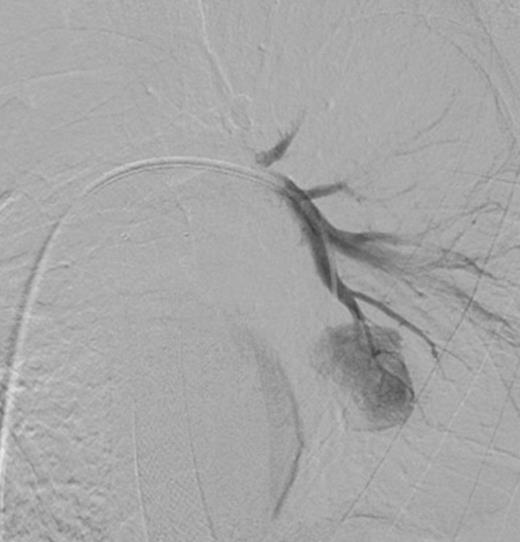

Digital subtraction angiography post deployment of the AVP 4 device in the PA branch feeding the aneurysm (arrow). No residual or collateral filling seen

Coronal reconstruction of CTPA taken 2 days after embolisation demonstrating successful ongoing exclusion of the PA aneurysm. Note the AVP (arrow) and continued filling of unaffected lower lobe segmental pulmonary arterial branches